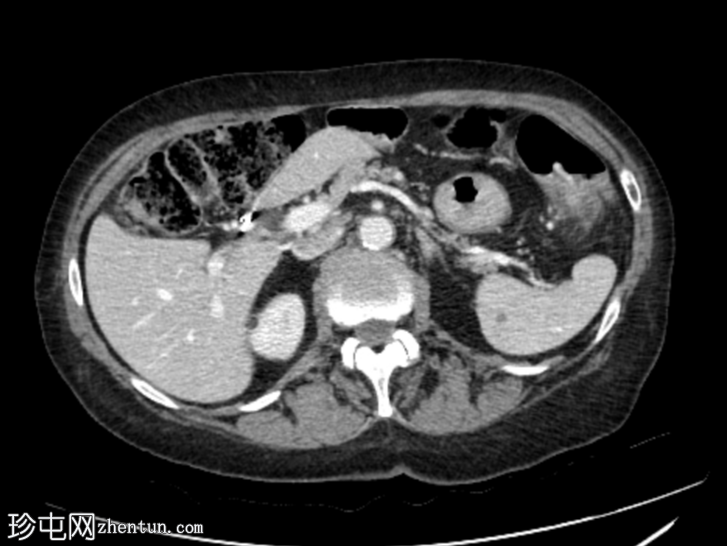

轴位增强扫描

动脉期

平扫图像显示左侧结肠脾曲处可见小憩室,伴结肠周围脂肪间隙条索状改变,提示急性结肠憩室炎。

动脉早期可见造影剂外渗,冠状位和矢状位最大强度投影(MIP)图像也可见,位于憩室炎同一部位,符合活动性出血表现。

随后的门静脉期和延迟期图像显示造影剂在结肠腔内积聚。